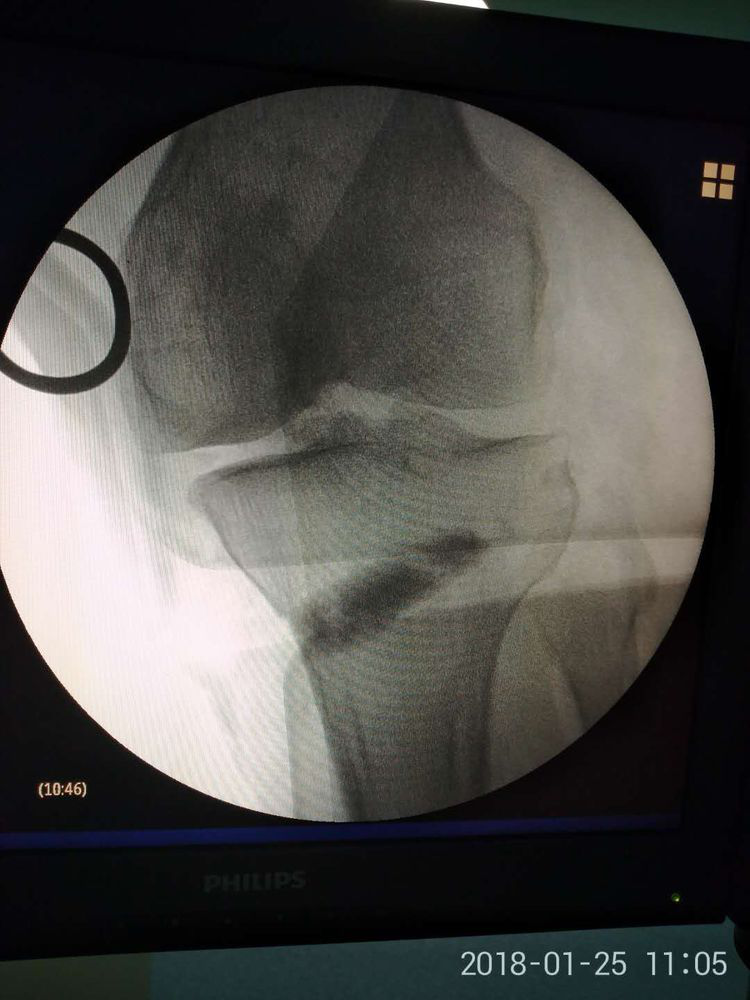

患者男,52歲,右膝關(guān)節(jié)疼痛、活動受限3年,加重1月。既往長期服用鎮(zhèn)痛藥物,近期關(guān)節(jié)腔內(nèi)注射玻璃酸鈉,膝關(guān)節(jié)疼痛癥狀進(jìn)行性加重,以致無法行走,患者為嚴(yán)重的膝關(guān)節(jié)內(nèi)翻畸形,保守治療無效,行膝關(guān)節(jié)置換術(shù)相對年齡較小,趙占富主任醫(yī)師決定采用"保膝"手術(shù)治療,膝關(guān)節(jié)內(nèi)外側(cè)切口均為4-5cm左右。

脛腓骨雙截骨平衡手術(shù)特點(diǎn):1、手術(shù)為微創(chuàng)手術(shù),創(chuàng)傷小,手術(shù)時(shí)間短,出血少,并發(fā)癥發(fā)生率低;2、脛骨近端為不全骨折,置入墊片后不影響下肢負(fù)重,可早期下地功能鍛煉;3、手術(shù)無需鈦板固定,費(fèi)用少;4、置入墊片為可吸收材料,無需取出,且不影響后期膝關(guān)節(jié)置換術(shù)。